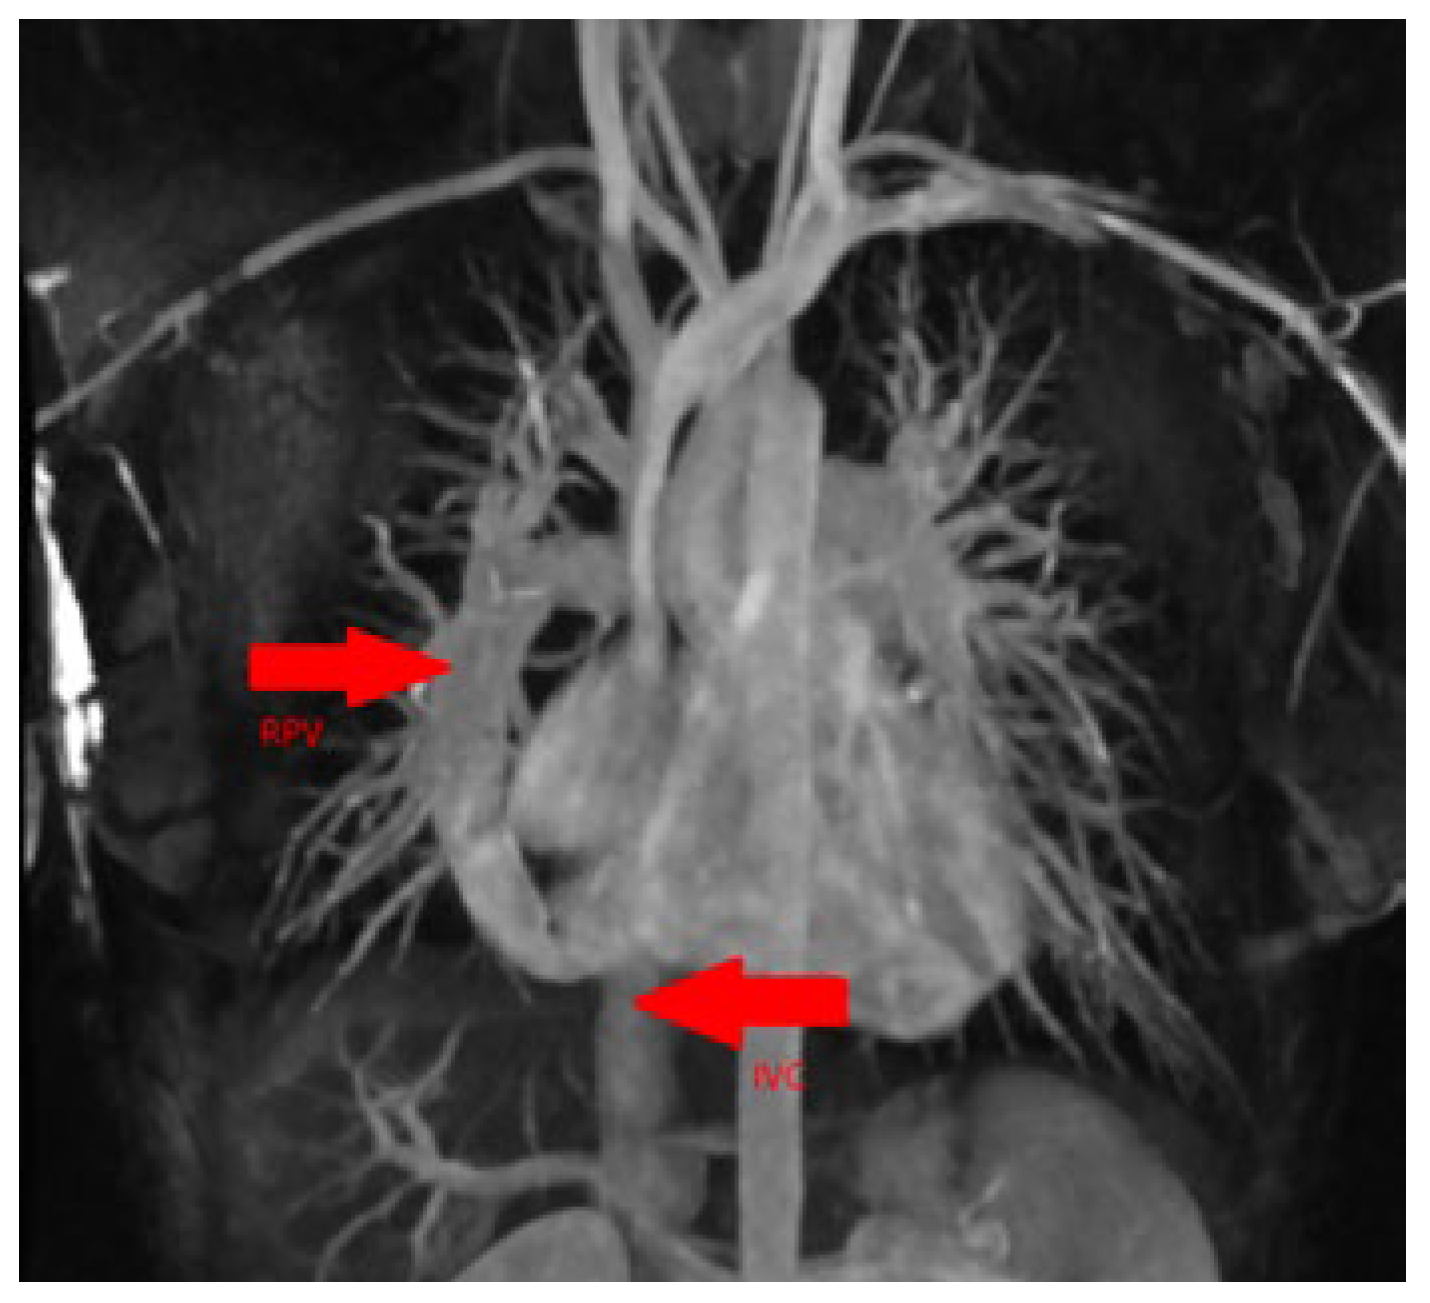

No pulmonary embolism was detected nor were there any signs of structural pneumopathy. Cardiac magnetic resonance imaging (MRI) confirmed the diagnosis of scimitar syndrome with measurement of a relevant left-to-right shunt (ratio of total pulmonary blood flow to total systemic blood flow [Qp/Qs] 2.0) (Figure 4).

Figure 4. Cardiac MRI confirming the diagnosis. IVC (arrow): inferior vena cava; RPV (arrow): right pulmonary vein.